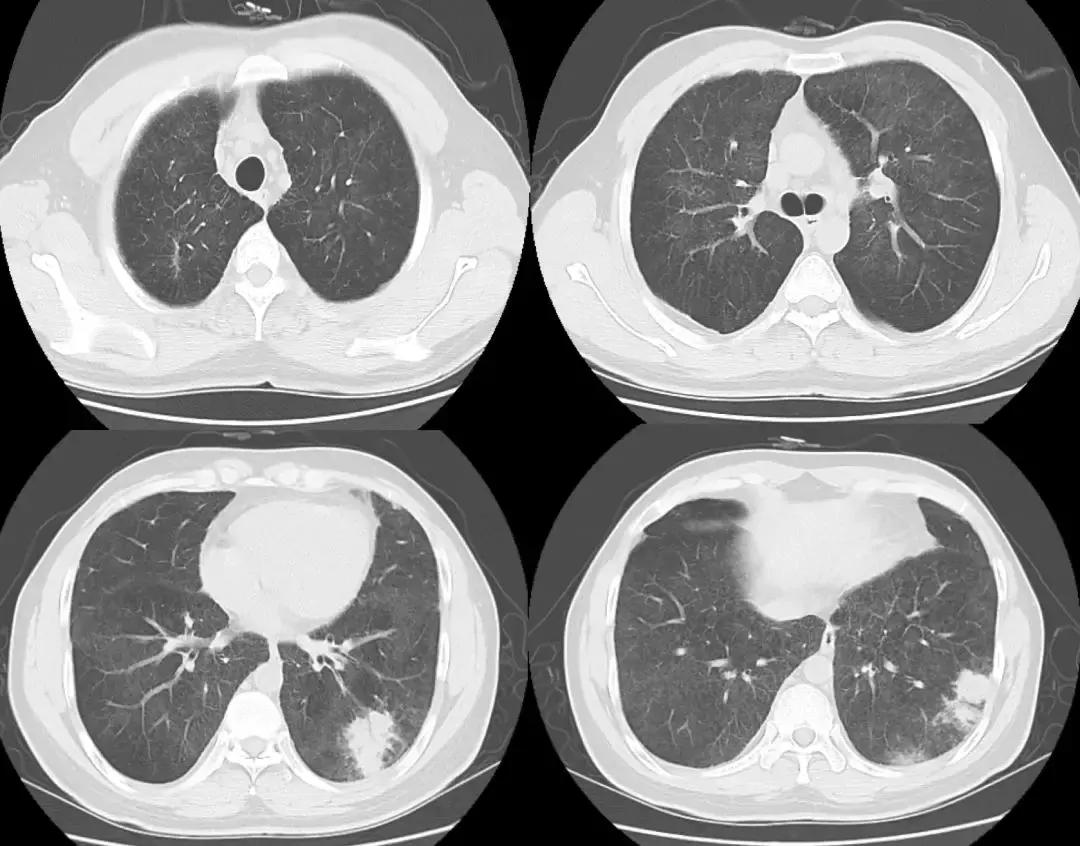

2018-01-22行支气管镜检查:示两侧支气管粘膜充血明显,可见少量白色分泌物,充分吸引;于左下叶生理盐水20ml灌洗2次,回吸收均约10余ml;左上叶、左下叶刷检,刷片共6张。(气管镜报告如下图)。

隆突 右上叶

右中叶 右下叶

左上叶 左下叶

支气管镜病理检查如下

复查胸部CT(2018-1-29),对比原片如下图:

1、两肺野弥漫病变较前未见明显变化,两肺上叶陈旧病变同前

2、左肺下叶片状密度增高影较前范围增大,密度增高

3、纵膈内多发淋巴结,大者位于气管隆突下,短径约1.1cm,较前未见明显变化;余基本同前。